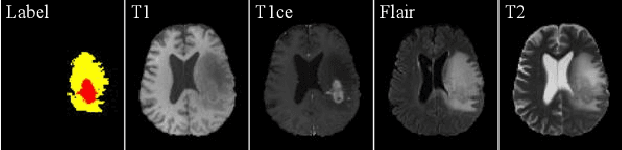

Abstract:Due to the difficulties of obtaining multimodal paired images in clinical practice, recent studies propose to train brain tumor segmentation models with unpaired images and capture complementary information through modality translation. However, these models cannot fully exploit the complementary information from different modalities. In this work, we thus present a novel two-step (intra-modality and inter-modality) curriculum disentanglement learning framework to effectively utilize privileged semi-paired images, i.e. limited paired images that are only available in training, for brain tumor segmentation. Specifically, in the first step, we propose to conduct reconstruction and segmentation with augmented intra-modality style-consistent images. In the second step, the model jointly performs reconstruction, unsupervised/supervised translation, and segmentation for both unpaired and paired inter-modality images. A content consistency loss and a supervised translation loss are proposed to leverage complementary information from different modalities in this step. Through these two steps, our method effectively extracts modality-specific style codes describing the attenuation of tissue features and image contrast, and modality-invariant content codes containing anatomical and functional information from the input images. Experiments on three brain tumor segmentation tasks show that our model outperforms competing segmentation models based on unpaired images.